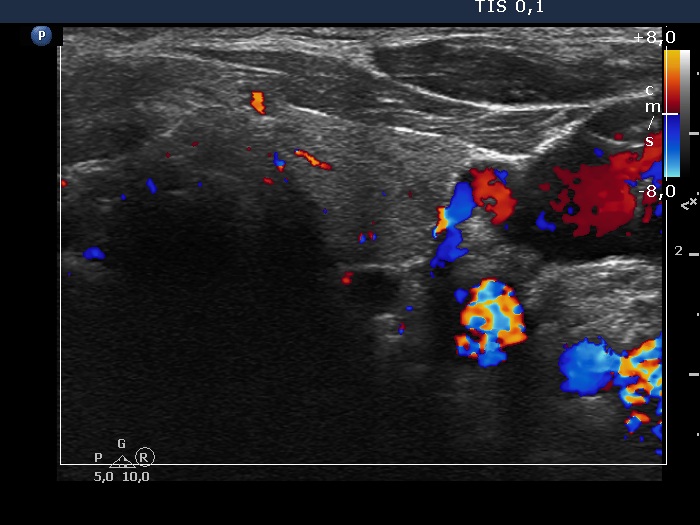

Parathyroid lesions - case 97 (ultrasonographic picture 9)

Left lobe, transverse scan, color Doppler mode. The vascularization is not specific.